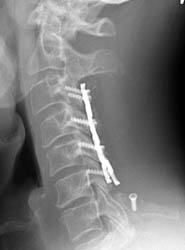

AP and lateral radiographs taken 5 days later, while still in the

hospital. Note migration of left C6 screw. It has loosened and fallen out. This

screw was not causing symptoms and decision was made to conservatively manage

the patient and keep in rigid cervical collar until the bone graft matured in

2-3 months.